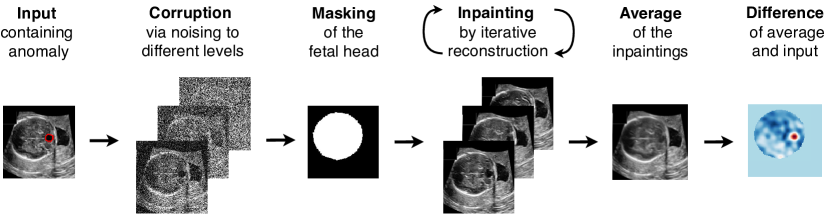

Existing approaches [31, 32, 15] have demonstrated the feasibility of supervised detection of fetal brain anomalies. However, these methods (i) require labels for the individual malformations, sometimes down to anatomical details [15], (ii) are bound to the detection of a closed set of frequent anomalies from the training data. To overcome these limitations, we present a proof-of-concept for the unsupervised detection of fetal brain anomalies based on Denoising Diffusion Probabilistic Models [10] (DDPMs). Specifically, we adapt existing reconstruction-based methods [30, 8] to build an inpainting-based Noise Agnostic Anomaly Detection (iNAAD) framework, involving averaging over reconstructions from multiple noise levels as in [8] and inpainting the fetal anatomy (see Fig. 1). To the best of our knowledge, no prior work has investigated unsupervised detection methods for fetal brain anomalies. Our approach requires access only to ultrasound images of normal fetal brains during training, which are more readily available than abnormal cases. In summary, we contribute 1) the first extensive evaluation of different noise types in DDPMs for the fetal ultrasound setting, 2) a diffusion-based algorithm iNAAD for unsupervised anomaly detection evaluated on a clinical dataset with a wide range of common fetal brain anomalies.

Following [28, 30, 8], we adopt a reconstruction-based anomaly detection approach, aiming to reconstruct input images using DPPMs trained on normal, anomaly-free, fetal ultrasound scans. Specifically, we apply the forward process to corrupt to , for a fixed , and then retrieve the reconstructed image from by the reverse process. Hyperparameter controls the level of noise degradation. Given the image at step in the forward process, we denote its corresponding reconstruction with the same steps in the reverse process as . The altered content between the input image and its reconstruction can therefore be interpreted as an anomaly indicator. To quantify these anomalies, we present the iNAAD algorithm, which is outlined in Alg. 1.

Inspired by [19], we constrain the reconstruction within the region of interest, i.e., the fetal brain in the image with inpainting. In particular, we apply a binary mask obtained with a pre-trained segmentation model [18] to ignore all the variations beyond the fetal brain. Given a pre-defined noise distribution and a trained denoiser , we define the inpainted reconstruction by,

During the forward process, the information content of is controlled by the noise level . Similar to [8], we aggregate reconstructions obtained by degrading with a range of multiple noise levels . By reconstructing all corrupted versions of and averaging these reconstructions, we obtain a final reconstructed image that integrates information from all reconstructed versions while reducing noise from individual reverse processes [8].

iNAAD requires only normal fetal brain ultrasound images for training. It identifies abnormalities by aggregating diffusion-reconstructed fetal brain images from various noise levels, incorporating an inpainting step to limit reconstruction changes in the fetal brain. The proposed method is summarised in Alg. 1.